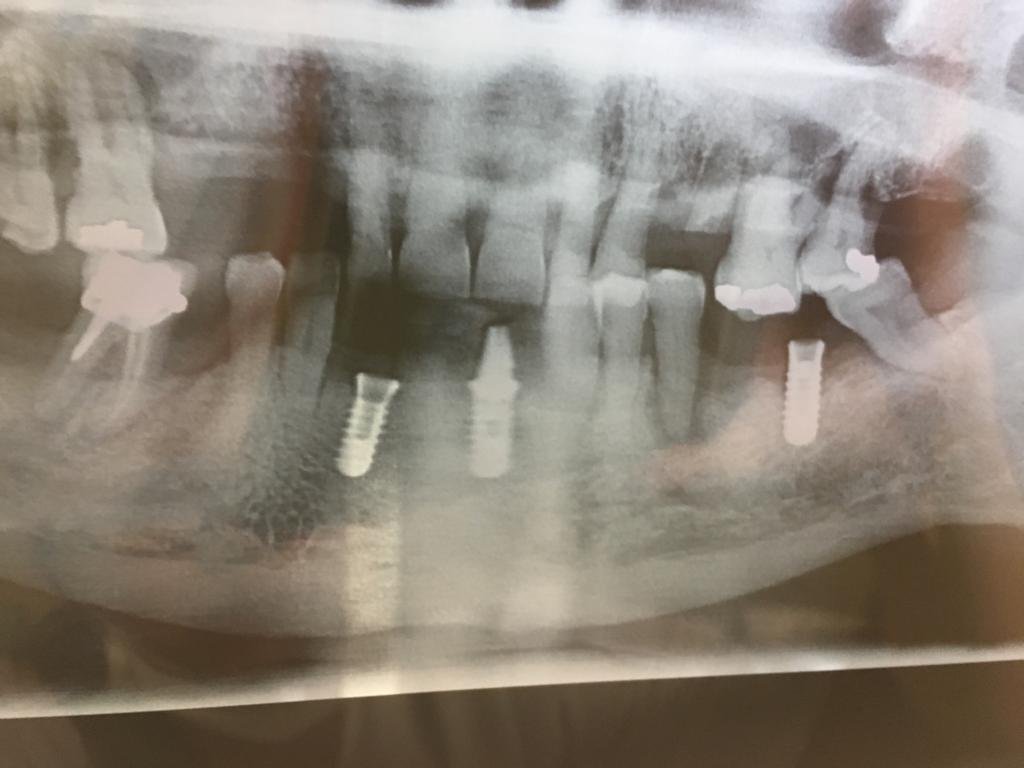

Buenas tardes quisiera saber si alguien me podría ayudar nose que marca de implantes tiene colocado el paciente. Hombre adulto 55 años. […]

Paciente com reabilitação total inferior com 6 implantes. qual marca?